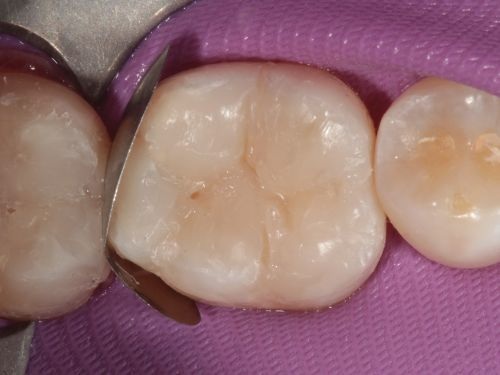

A 35-year-old male presented to the clinic to replace some inadequate restorations, one of which was for the lower right first molar (Fig. 1). For this tooth, the molar was restored with composite resin using the direct technique. The operative field was isolated, the old restoration was removed, and surface hybridization was completed using Futurabond U universal adhesive from Voco (Fig. 2). After placing a sectional matrix and a spacer ring, the composite resin (Voco’s GrandioSO 4U, shade A2) was placed in the proximal box with a thickness less than 4 mm, which is the maximum recommended thickness for the chosen material (Fig. 3). Additional increments of composite resin were applied to complete the anatomical stratification. The final morphology was sculpted, followed by light-curing to ensure complete polymerization (Fig. 4). The rubber dam was removed (Fig. 5), and the occlusion was adjusted using a finishing carbide bur with 12 blades (Fig. 6). Finishing and polishing was completed, with the final result shown in the Figures 7 and 8.